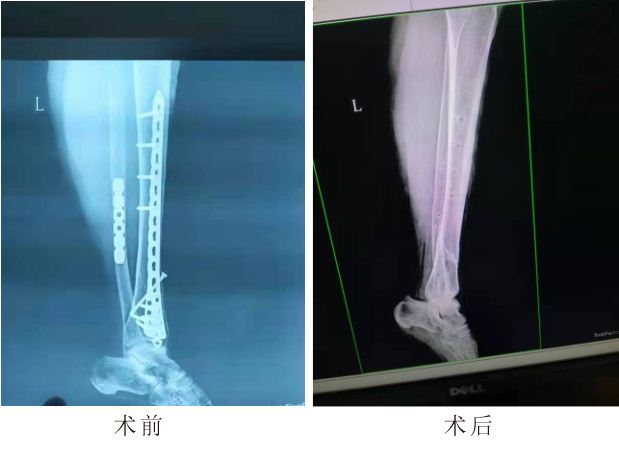

1月5日,内江市中医医院第15中医专家团队(肖启树、陈安丽、张云洪)在中医院各部门的统筹协调安排下,运用断钉滑钉取出器,成功的在受援医院:资中县龙结镇卫生院为一名陈旧性胫腓骨骨折,内固定螺钉断裂患者,进行了内固定物取出术。手术顺利,术中未造成患者二次损伤,术后照片显示:内固定完整去除,骨纹理贯通,无金属异物残留。这是内江市中医医院在中医强基层“百千万”行动中,首次在受援基层医院开展骨科手术。彰显了医院在骨科方面的技术实力,在面临各种复杂病情变化情况下,沉着冷静,处变不惊,不断更新技术设备为患者带来更好、更适合、更加个性化的的诊疗理念。

该患者为资中县龙结镇农民,于2018年在成都工地打工时不慎受伤,致右胫腓骨粉碎性骨折,在成都某一三甲医院行手术治疗,病情好转出院,评估为9级伤残,此后患者在家休养,逐渐患者发现右小腿皮肤下方螺钉触手可及,有活动感,动辄痛甚,没有引起重视。最近,患者右小腿不适感加剧,遂前往资中县龙结镇卫生院就诊,以“右胫腓骨陈旧性骨折”收入住院,经过系列检查,资中县龙结卫生院院长赵万里积极与支援中医专家组长肖启树进行会诊、讨论、病例分析后诊断右胫腓骨陈旧性骨折(螺钉变形断裂)。考虑到右胫腓骨陈旧性骨折,术后3年,病史较长,患者重体力劳动者,不排除术后再次损伤可能,故造成内固定螺钉疲劳,断裂可能性极大,经过术前的充分准备,内江市中医医院第15小组团队团结协作,肖启树副主任医师主刀,陈安丽护士长负责器械,心内科张云洪医师负责心电监护,动态掌握监测患者生命体征,保障生命安全。整个手术过程非常顺利,术后患者功能恢复良好。

图片

(术前术后片子)